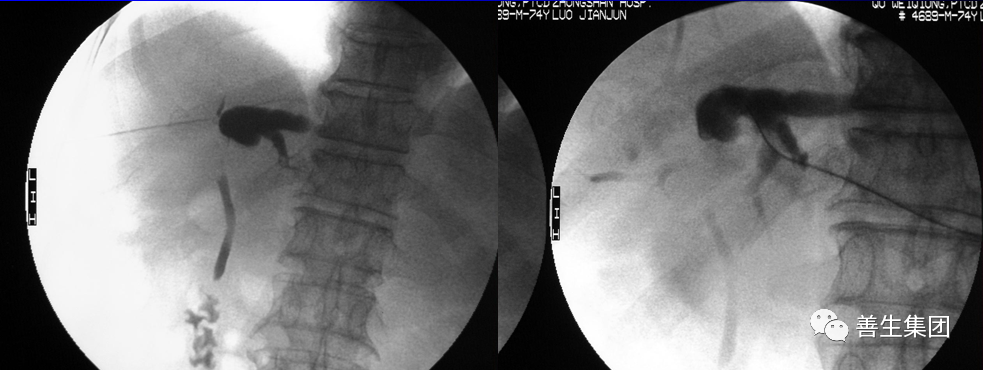

胆囊MT术后,梗阻性黄疸。

左肝MT,梗阻性黄疸,累及肝门,引流分支,不彻底。

引流+支架后黄疸先下降后上升。